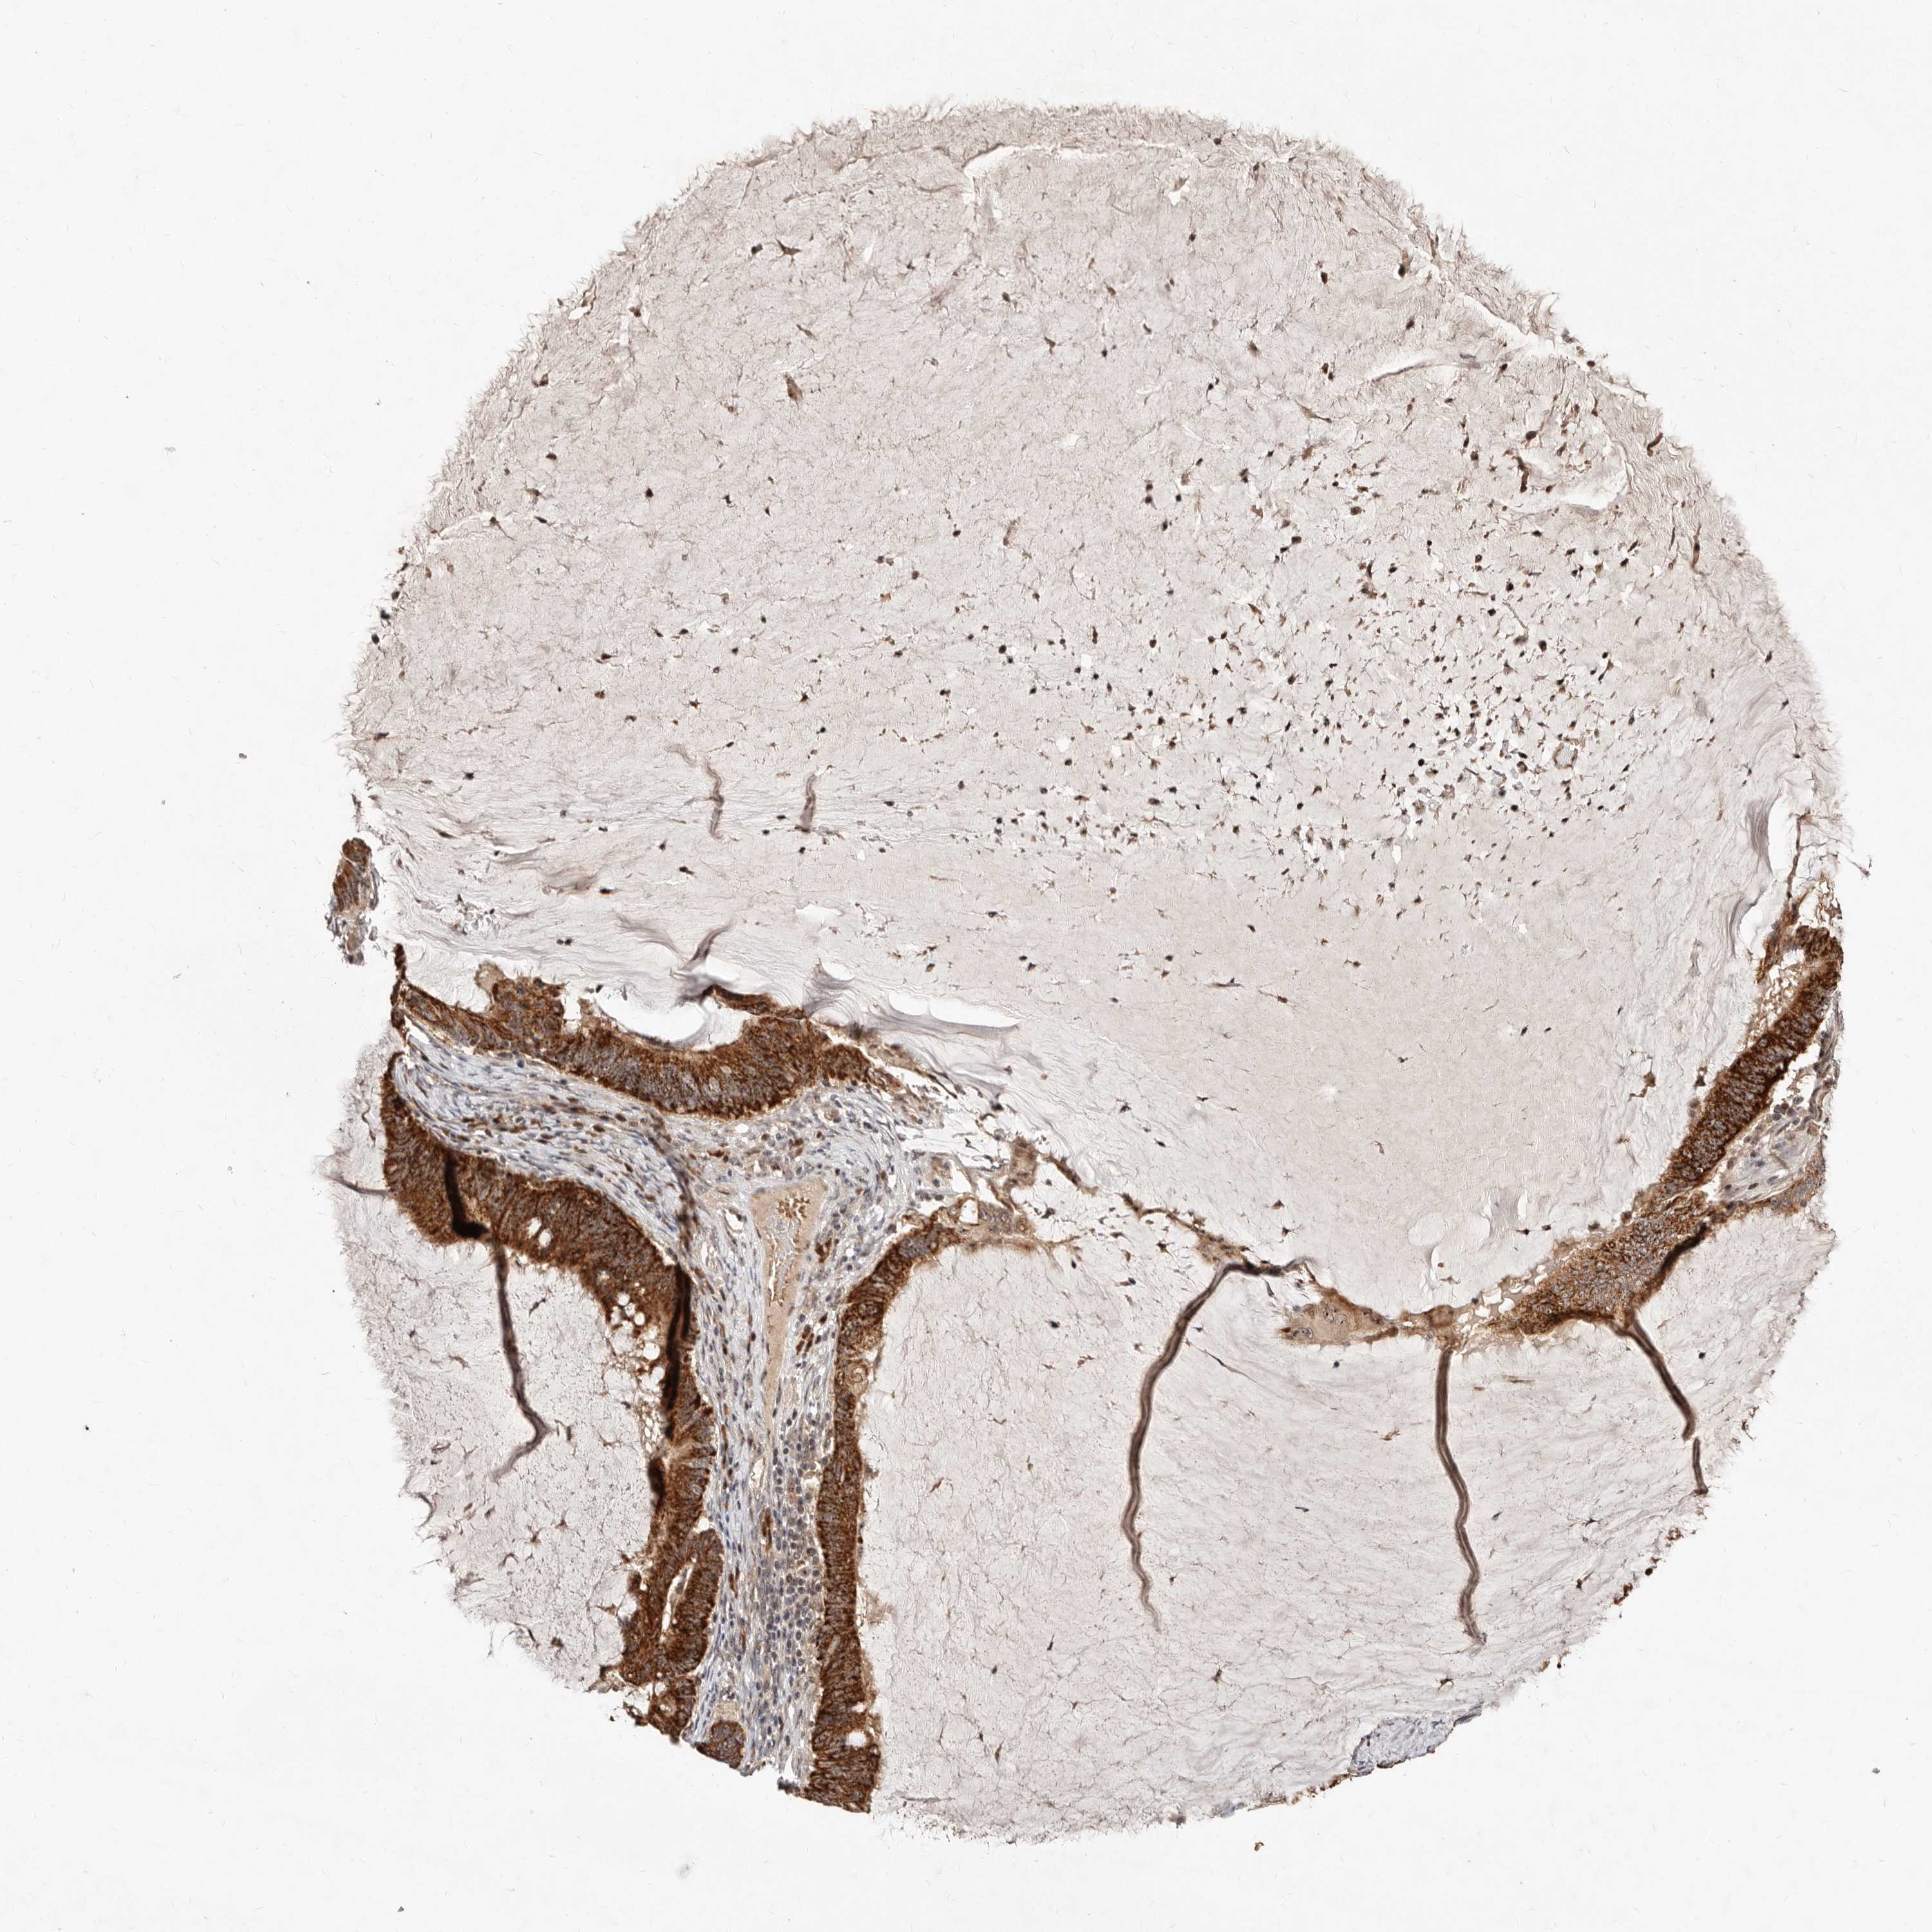

OVARIAN CANCER - Protein expressioni

A mouse-over function shows sample information and annotation data. Click on an image to view it in a full screen mode. Samples can be filtered based on level of antibody staining by selecting one or several of the following categories: high, medium, low and not detected. The assay and annotation is described here.

Note that samples used for immunohistochemistry by the Human Protein Atlas do not correspond to samples in the TCGA dataset.

Antibody stainingi

Antibody staining in the annotated cell types in the current human tissue is reported as not detected, low, medium, or high, based on conventional immunohistochemistry profiling in selected tissues. This score is based on the combination of the staining intensity and fraction of stained cells.

Each image is clickable and will lead to virtual microscopy that enables deeper exploration of all samples and also displays staining intensity scores, fraction scores and subcellular localization as well as patient and tissue information for each sample.

Antibody HPA029165

Antibody HPA029167

Antibody CAB028574

Staining

High

Medium

Low

Not detected

Intensity

Strong

Moderate

Weak

Negative

Quantity

>75%

75%-25%

<25%

None

Location

Nuclear

Cytoplasmic/membranous

Cytoplasmic/membranous,nuclear

Cystadenocarcinoma, serous, NOS

Carcinoma, endometroid

Cystadenocarcinoma, mucinous, NOS

Carcinoma, NOS